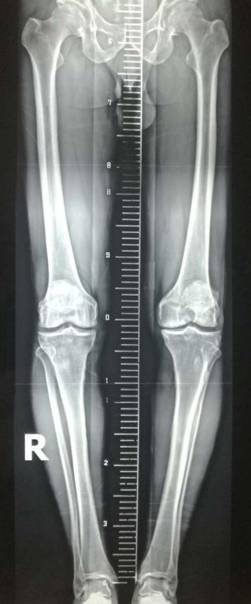

胫骨高位截骨治疗膝关节骨关节炎

优点:创伤小,疗效确切,适合生活方式活跃的年轻患者。

术前术后对比

全膝关节翻修术

全髋关节翻修术